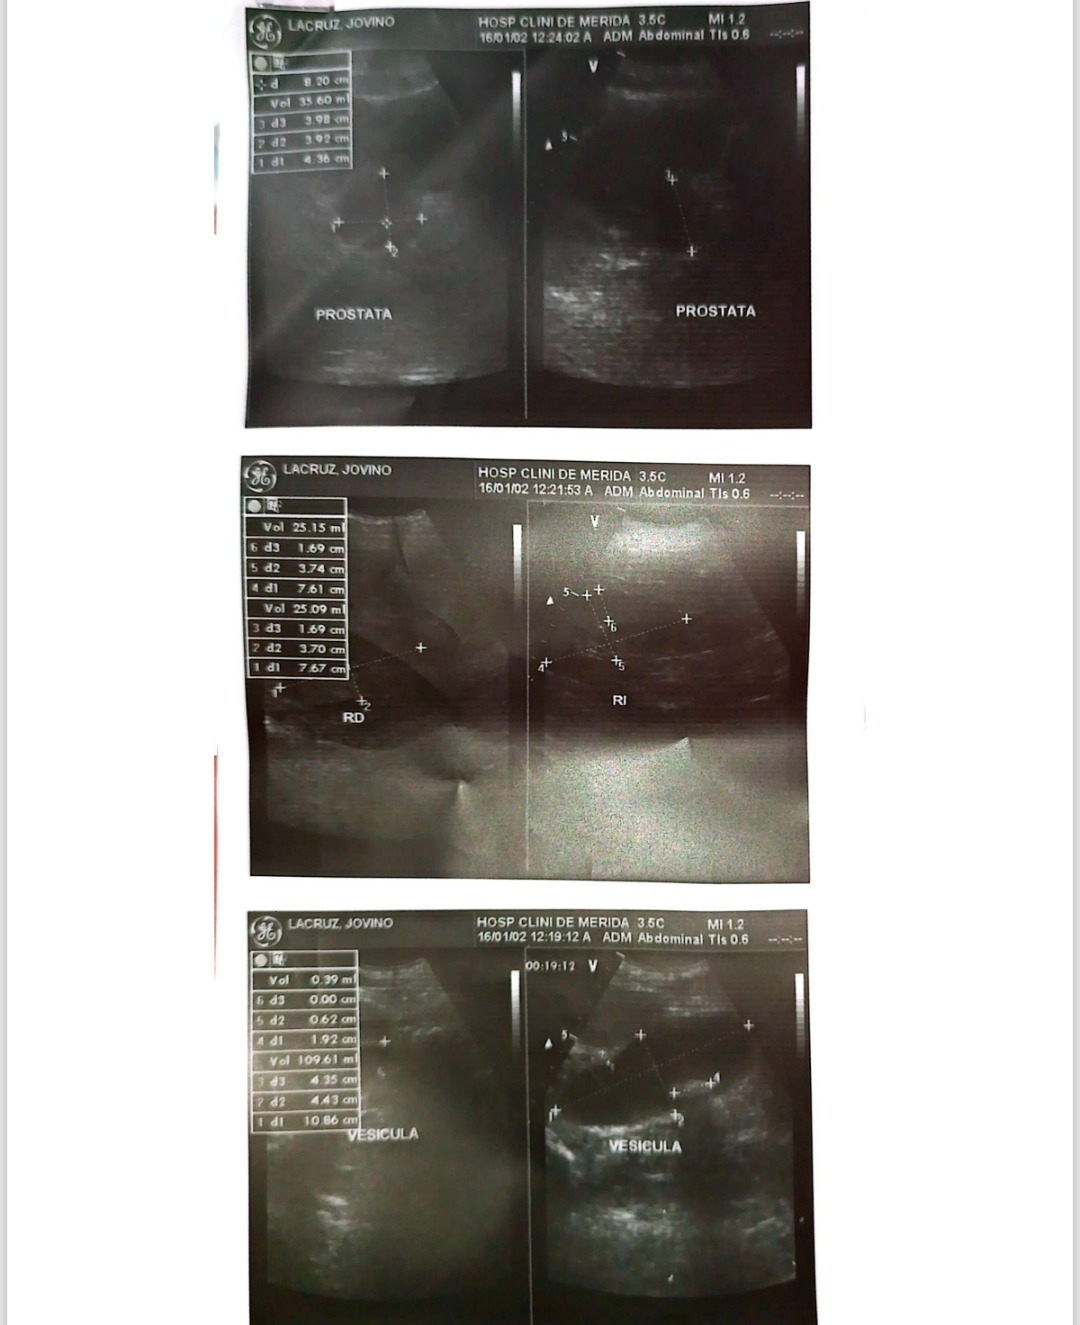

My name is Ana Lisabel Lacruz Mendoza, and I am raising funds to cover the medical expenses of my father, Jovino Lacruz (ID V-2.453.801), who is 91 years old. He recently underwent emergency surgery due to acute cholecystitis with gallstones and hydrocholecyst, along with bilateral degenerative kidney changes and grade I prostate enlargement.

The diagnosis was confirmed through an abdominal and pelvic ultrasound performed on October 24, 2025, by Dr. María Fernanda Marquina at Serranía Unidad de Imagenología C.A. (report attached).

We’ve attached the emergency medical report, surgical evaluation, and ultrasound results for full transparency.

Mi nombre es Ana Lisabel Lacruz Mendoza, y estoy recaudando fondos para cubrir los gastos médicos de mi padre, Jovino Lacruz, cedula V-2.453.801, de 91 años, quien fue sometido recientemente a una cirugía de emergencia debido a una colecistitis aguda con litiasis vesicular e hidrocolecisto, además de cambios degenerativos renales bilaterales y crecimiento prostático grado I, por su condición su cirugía debía hacerse los más rápido posible para evitar complicaciones que podían poner en riesgo su vida, ya que también padece de una Cardiopatía Isquémica lo que hizo aún más critica la situación.

El diagnóstico fue confirmado mediante un estudio de ultrasonido abdomino-pélvico realizado el 24 de octubre de 2025 por la Dra. María Fernanda Marquina en el Servicio de Imagenología de Serranía Unidad de Imagenología C.A (Anexo)

Adjunto el informe médico de emergencia, valoración de cirugía y ultrasonido abdomino-pélvico para mayor transparencia. Cualquier aporte, por pequeño que sea, será de gran ayuda para nosotros en este momento tan difícil. Gracias por tu solidaridad y por compartir esta campaña.